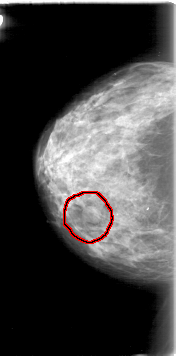

FILE: D_4013_1.RIGHT_MLO.OVERLAY

TOTAL_ABNORMALITIES 1

ABNORMALITY 1

LESION_TYPE MASS SHAPE LOBULATED MARGINS OBSCURED

ASSESSMENT 0

SUBTLETY 5

PATHOLOGY BENIGN

TOTAL_OUTLINES 1

BOUNDARY